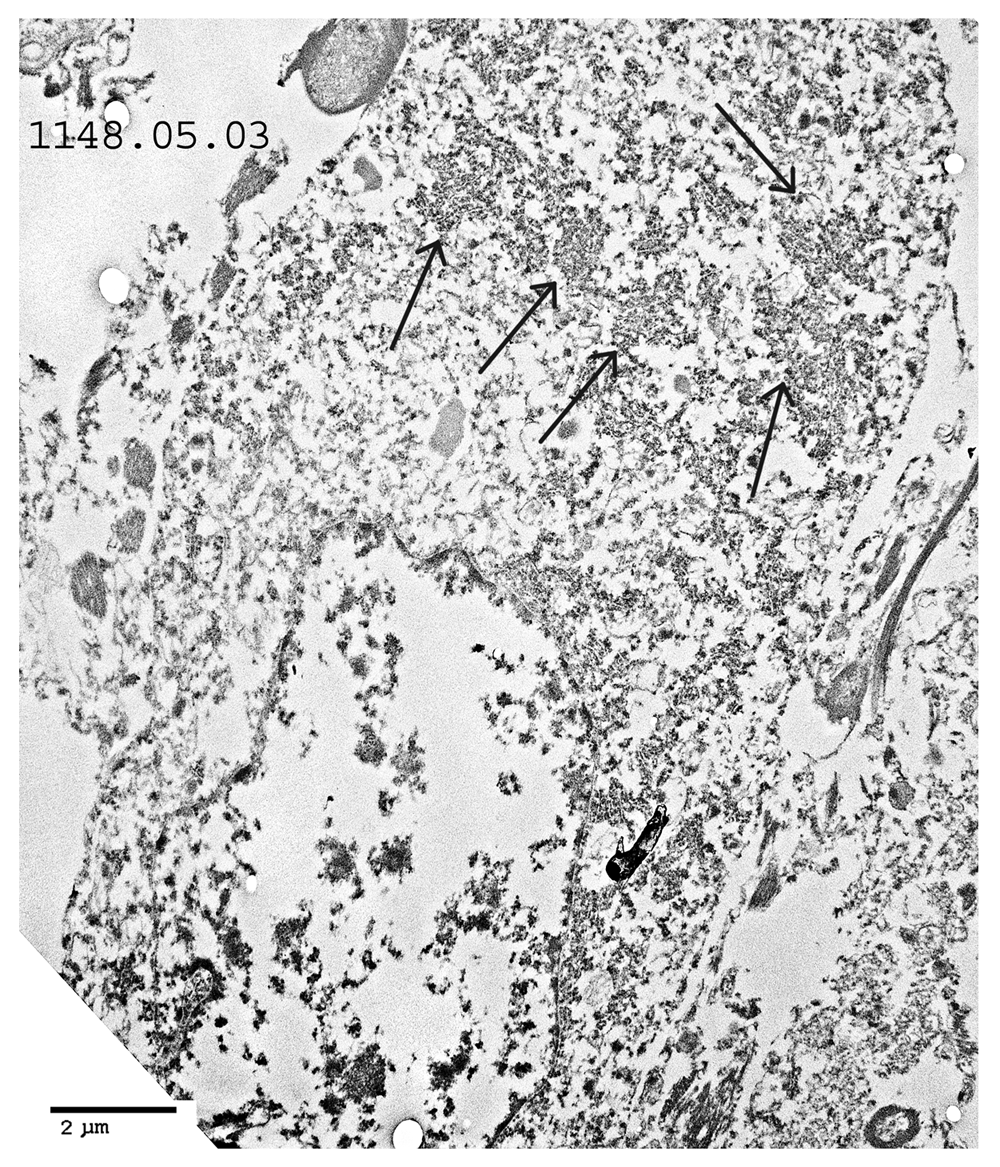

TEM changes were observed in the brainstem neurons in the PD cases and in the spinal cord motor neurons in the poliomyelitis cases. TEM of PD neurons at low magnification showed advanced apoptosis. There were almost ‘empty’ nuclei with clumped chromatin and multiple cytoplasmic virus factories. Few cytoplasmic organelles remained (Figure 1 and Figure 2). VLP were found by TEM in the nuclei and cytoplasm in the neurons of all the PD cases studied. The VLP were similar in morphology to the VLP we described in the brain of encephalitis lethargica, which had been confirmed to be a strain of enterovirus by molecular analysis1. The cytoplasmic virus factories in PD neurons consisted of large numbers of VLP interspersed with irregularly shaped endoplasmic reticulum membranes and embedded in virus factory (Figure 3 and Figure 4). VLP were observed attached to the membranes (Figure 3). The average measurements of the cytoplasmic VLP in Figure 3 and Figure 4 were both 31 nm (Table 1). Cytoplasmic virus factories in other PD neurons consisted of incomplete VLP at an early stage of assembly (Figure 5, see Discussion).

In the cases of human poliomyelitis, motor neurons of the spinal cord showed cytoplasmic virus factories and apoptosis similar to that shown in PD neurons (Figure 8–Figure 10). Intranuclear virus particles were found that were similar to the VLP in morphology and diameter to those found in the brain of the PD cases (Figure 11).

Low magnification of a motor neuron. Cytoplasmic virus factories are shown (arrows). The nucleus shows severe apoptosis.

A cytoplasmic virus factory, showing strands of endoplasmic reticulum and incomplete virus particles embedded in amorphous matrix.

The results of TEM of PD brain are comparable to the TEM finding of virus particles found in cell cultures infected with poliovirus and coxsackie virus1. The VLP found in PD brain are also comparable to the VLP in brain from encephalitis lethargica patients1, and the virus particles found in this study in human spinal cord neurons in cases of human poliomyelitis. We had confirmed the finding of enterovirus in encephalitis lethargica brain by the demonstration of a partial enterovirus nucleotide sequence in brain tissue1. In the present study, the observation that the VLP in many of the cytoplasmic virus factories in the PD cases are larger than the cytoplasmic ribosomes from control cases was confirmed by statistical analysis (Table 1 and Table 4). In certain PD cases, the cytoplasmic factories consisted of incomplete VLP measuring approximately 20 nm. There was also a membrane component to the virus factories (Figure 3 and Figure 5). We observed that similar cytoplasmic virus factories were in the human spinal cord neurons infected with polio virus (Figure 8–Figure 10). These findings suggest that the VLP in PD represent an enterovirus infection. Intranuclear VLP, measuring approximately 40 nm, were observed in the nuclei of motor neurons in cases of poliomyelitis (Figure 11).